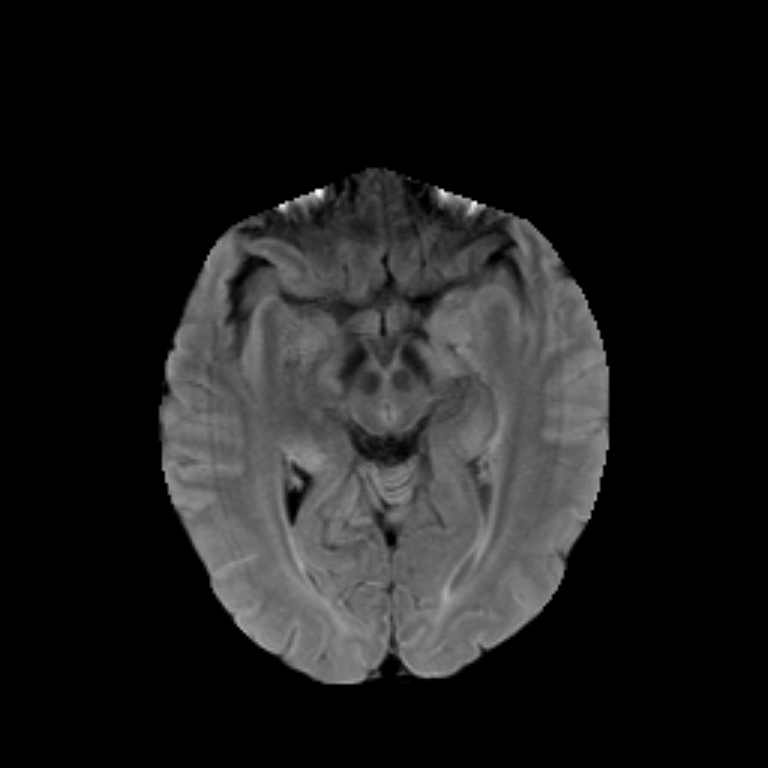

The dataset used for development was obtained from The Cancer Imaging Archive (TCIA) and involved 110 cases of lower-grade glioma patients. Registers brain MR images with manual FLAIR abnormality segmentation masks are published as a Kaggle Dataset lgg-mri-segmentation.